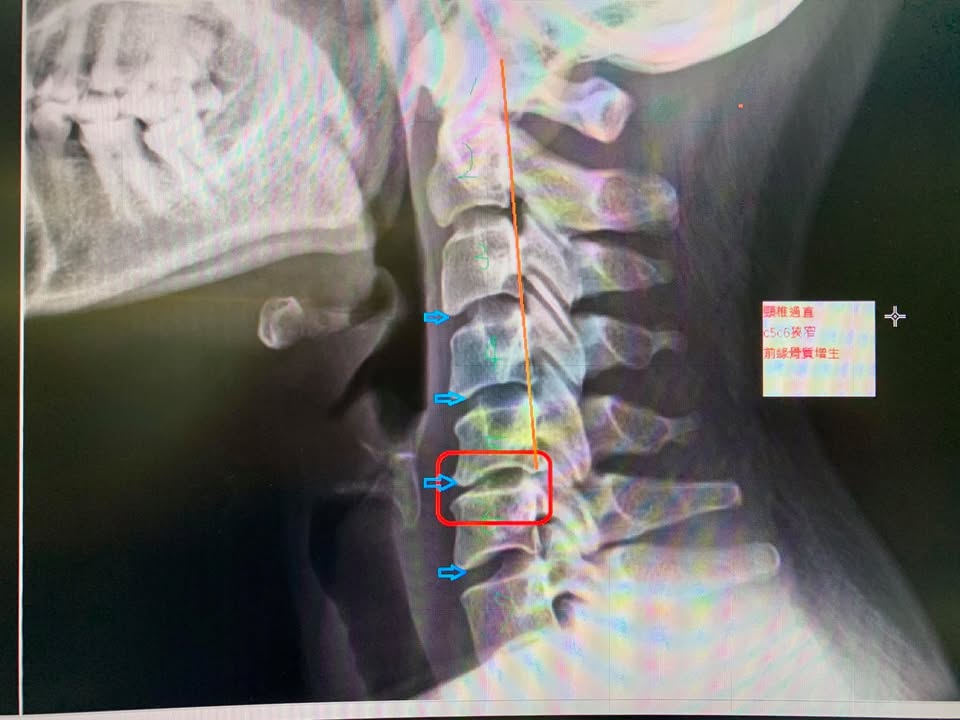

台北吳小姐抱怨肩頸疼痛,左邊最痛,左邊上臂疼痛,晚上睡覺非常痛,但是一直都沒辦法明顯改善,特別是開車時候疼痛到懷疑人生,會拉不住方向盤那麼恐怖😱,錐心刺骨四個字形容,經過先生介紹來診治療,來診前已經疼痛四個月,症狀在一兩週迅速惡化,X光片側位明顯發現患者頸椎過直,第四第五第六前面有一些骨刺,特別是第五跟第六椎間隙很窄,結合患者臨床症狀跟理學檢查

❇️診斷:C5C6壓迫左側神經根